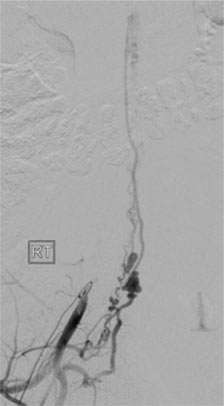

Depending on the lesion, the best treatment plan changes. For intramedullary AVMs, partial or palliative treatment is sometimes an option since complete obliteration may carry a much higher chance of causing neurological deficits than conservative management or partial treatment (Figure 3).

The treatment strategy includes catheter embolization, surgical resection, radiation, and/or a combination these modalities.

Figure 3: A palliative / partial Catheter Treatment for a Spinal AVM.